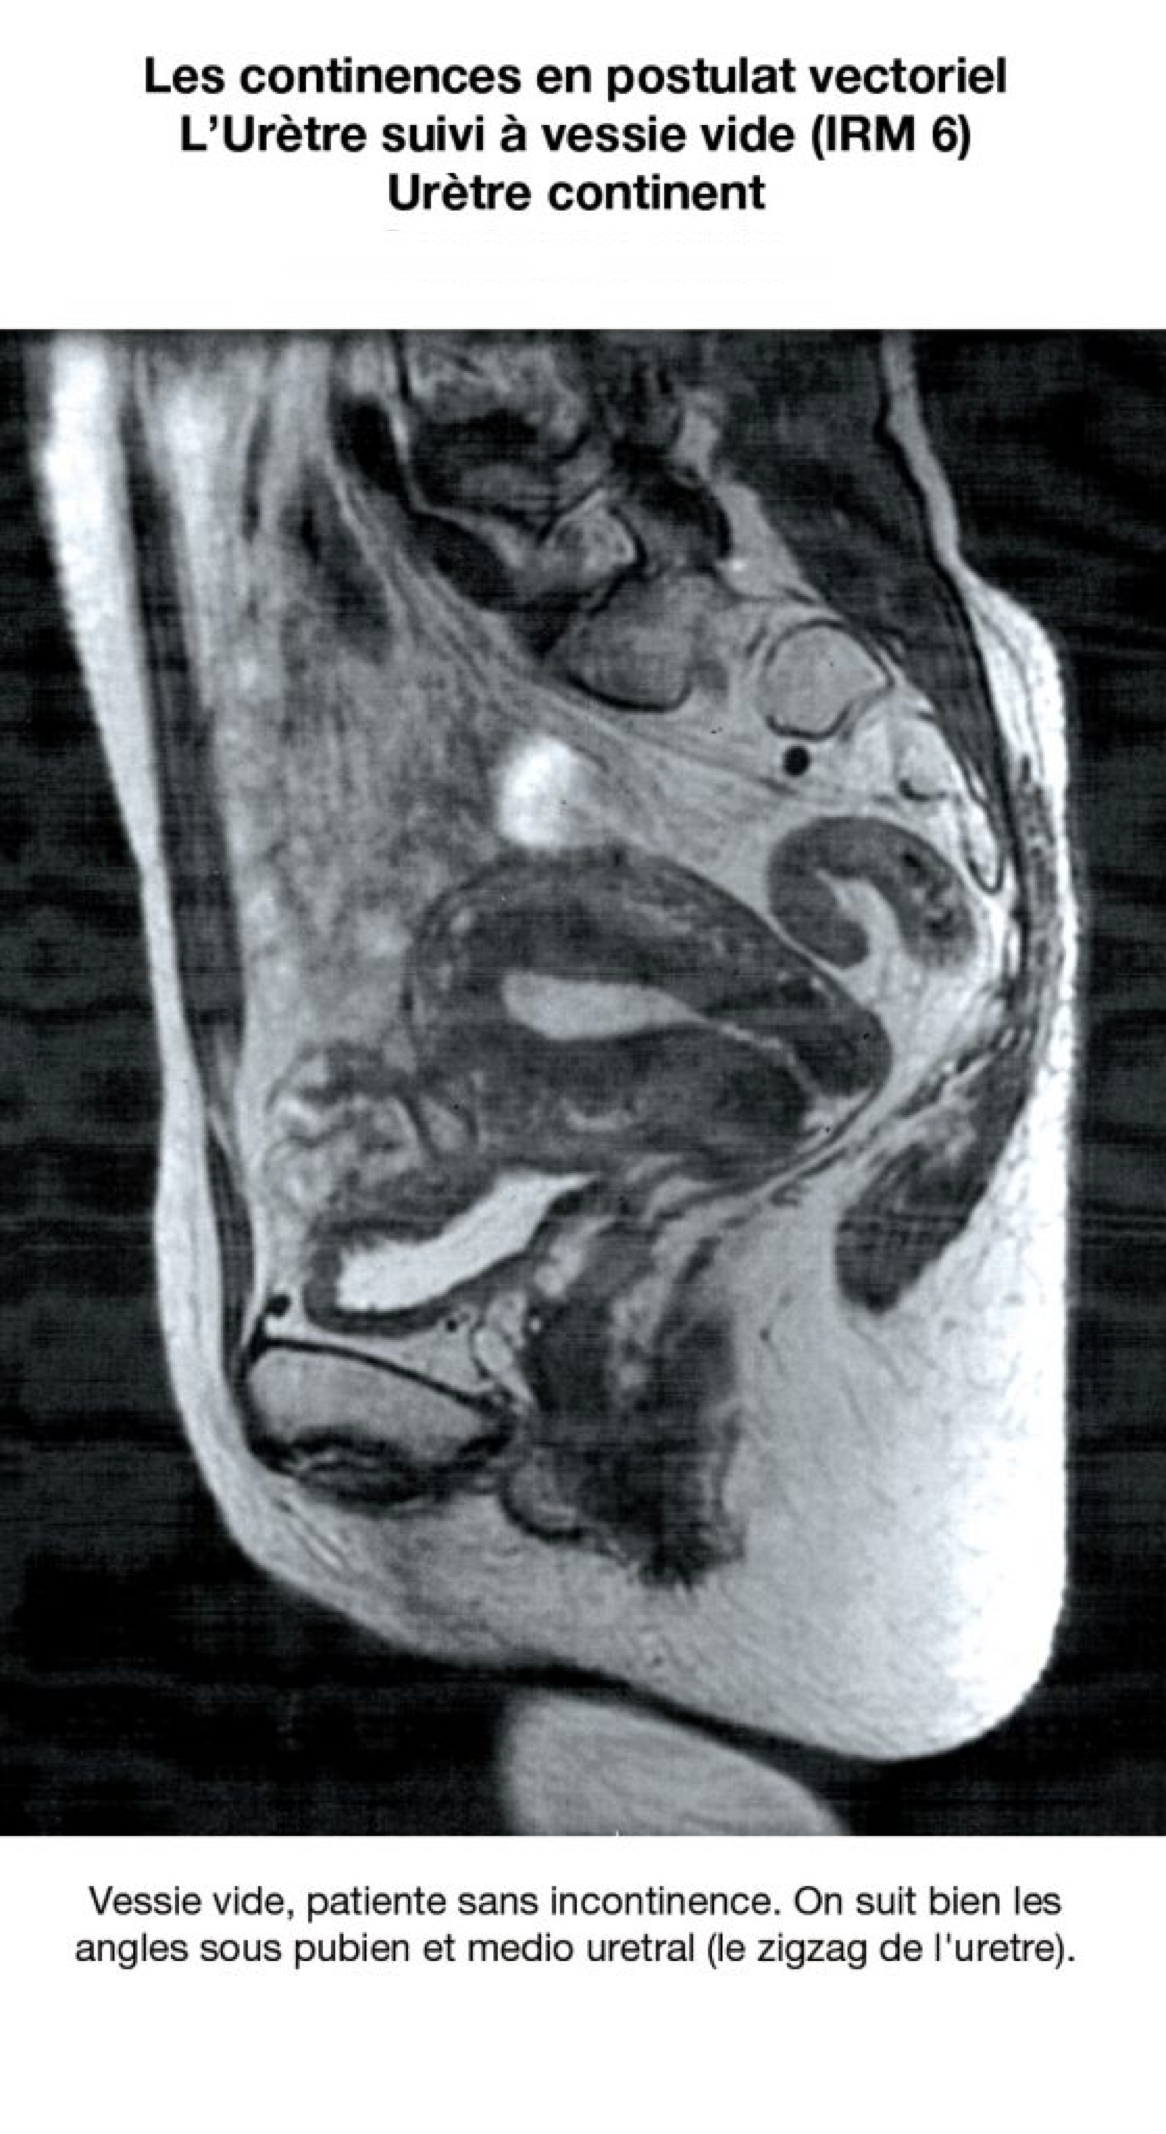

En postulat vectoriel, leur rôle essentiel pourrait être (???) celui de propriocepteurs ; et ils accentueraient et participeraient aux effets de clôture lors des glissements du tissu visco élastique pelvien. Divers arguments plaident en faveur de ces hypothèses : Pour l’urètre : 25% des vessies sont continentes à sphincter ouvert (ref 5). L’urètre continent de l’IRM n’est pas rectiligne. Il décrit un trajet en zigzag et la distance uretro pubienne faible. (Sa plicature peut être un mécanisme de continence). L’urètre continent n’est rectiligne que lors de l’incontinence physiologique, la miction (uretrographie mictionnelle).

14. Le zigzag urétral